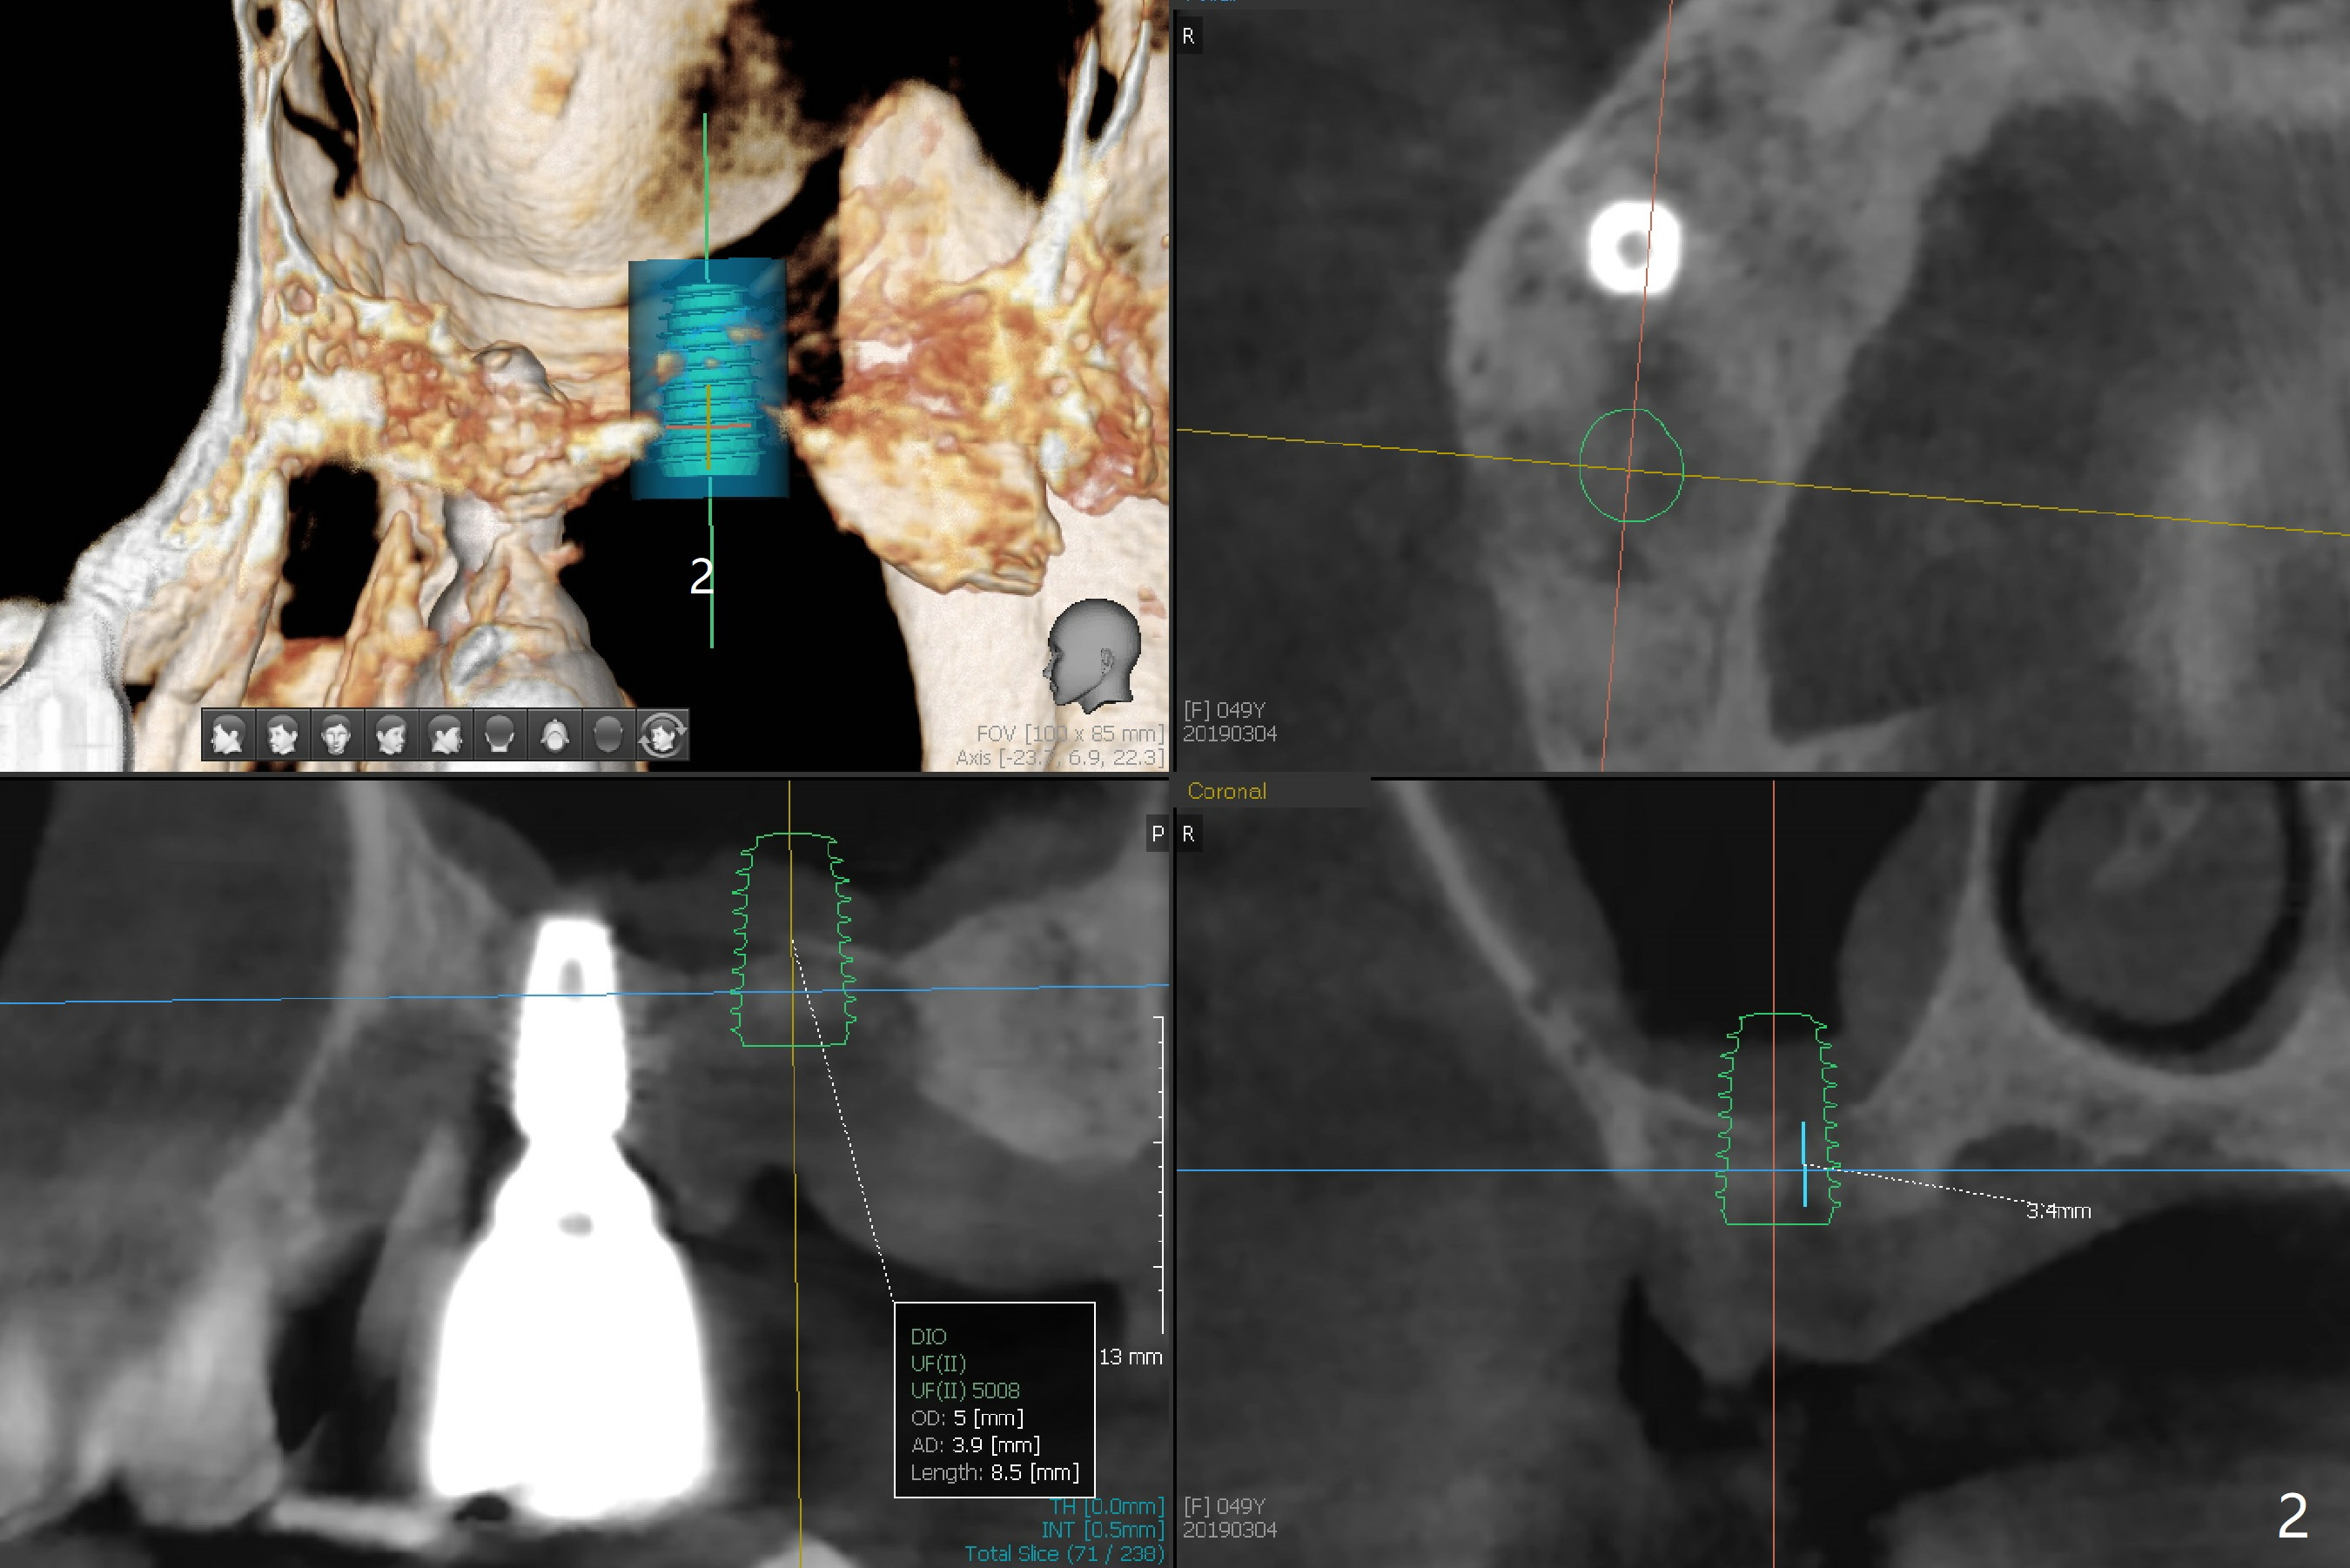

Implant